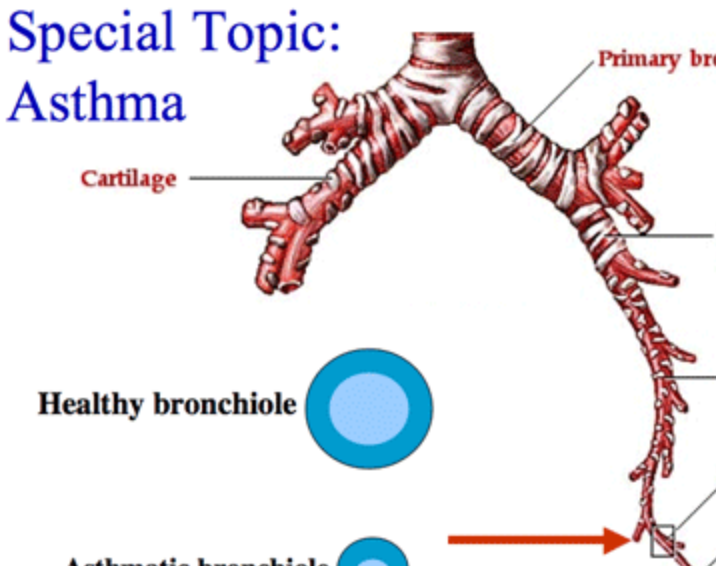

Cricoid cartilage

Bronchiole

Terminal bronchiole

Respiratory bronchiole